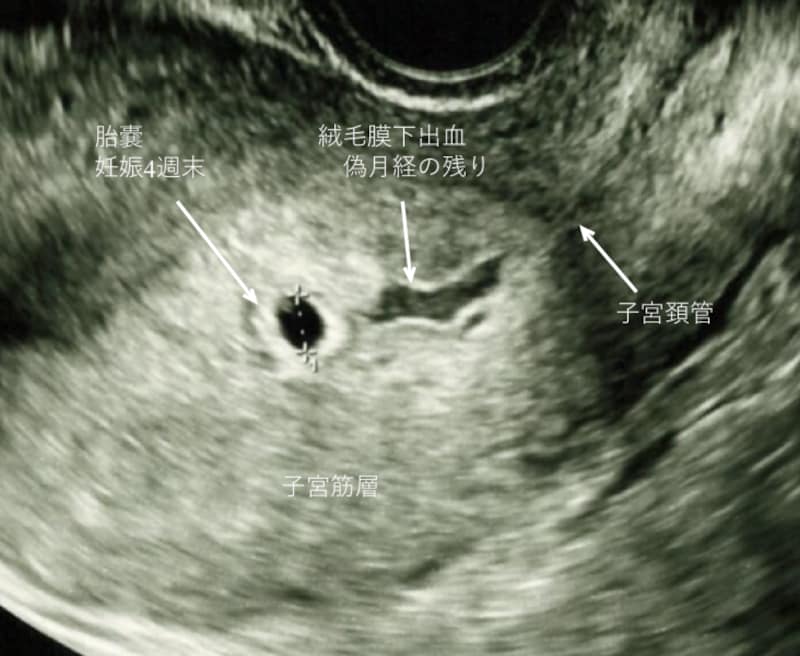

妊娠初期の出血4.絨毛膜下出血(血腫)

超音波検査で胎嚢が見え始めてから、胎嚢周囲に液体の貯留を認めることがあります。この場合、「子宮内に出血の痕がある」「子宮の壁と胎児の袋の間に血が溜まっている」などと説明があります。

偽月経の出血が、子宮内に残っている程度であれば、通常生活は問題ありませんが、胎児心拍が確認できる頃になっても、腟出血が続き、胎嚢の周囲で、新たな出血を繰り返している場合には、安静、休業の指示や、薬が処方されることもあります。